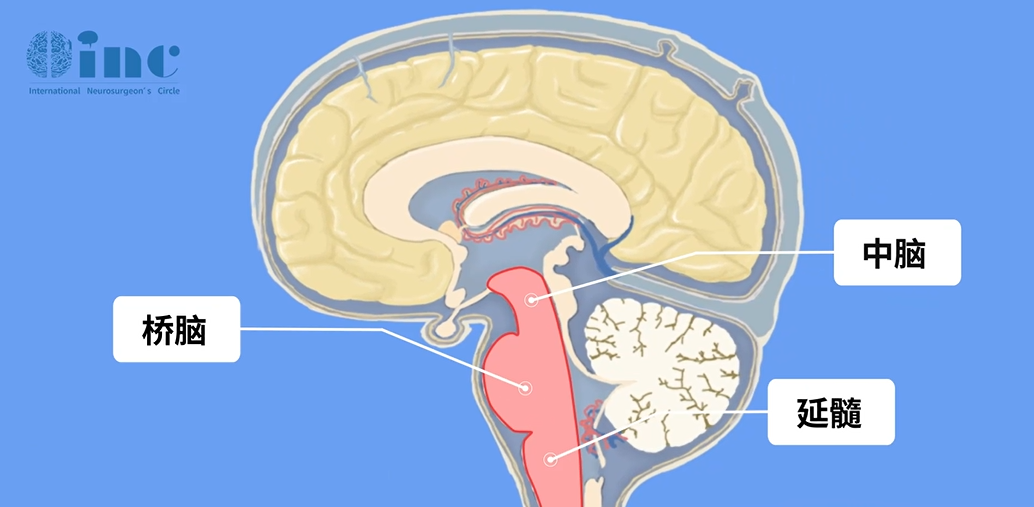

01 延髓是怎样一种存在

延髓位于大脑的最底部,经枕骨大孔与脊髓相连,是神经信号上下传导的核心通道。作为人体的生命中枢,延髓直接调控心跳、呼吸、血压等维系生命活动的基本生理功能。